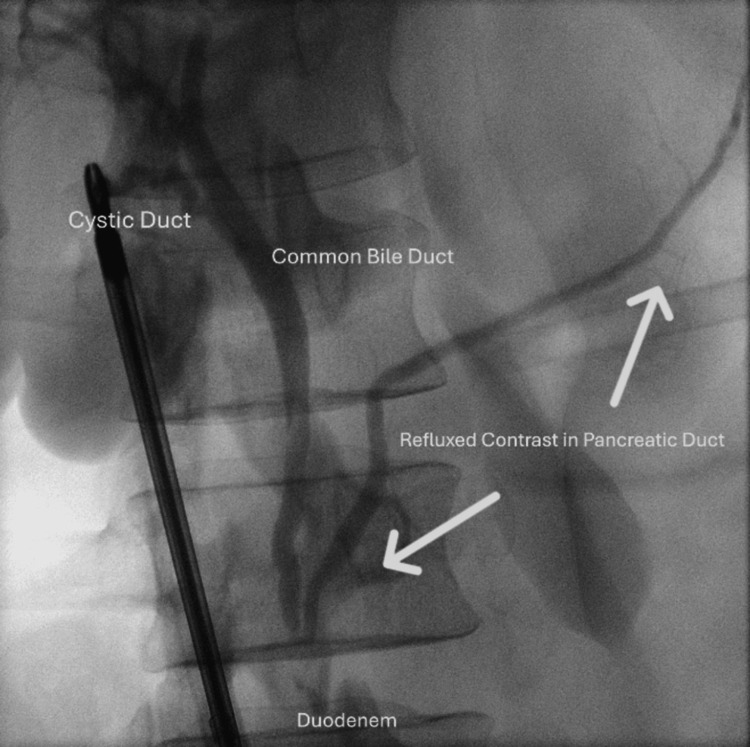

Intraoperative cholangiography (IOC) is frequently performed during laparoscopic cholecystectomy to delineate biliary anatomy and detect choledocholithiasis. While generally safe, postoperative pancreatitis following IOC is an uncommon and under-recognized complication. We report the case of a 41-year-old male patient who presented with postprandial pain on a background of symptomatic gallstones. Preoperative blood tests, including liver function tests, were unremarkable, and ultrasound demonstrated gallstones with a non-dilated common bile duct (CBD). He underwent an uncomplicated laparoscopic cholecystectomy with IOC, which revealed contrast reflux into the pancreatic duct. The following day, he developed severe epigastric pain radiating to the back, nausea, vomiting, tachycardia, and low-grade fever. Blood tests showed elevated lipase (2000 U/L) and deranged liver function. Computed tomography (CT) cholangiogram confirmed acute interstitial pancreatitis without evidence of bile leak, choledocholithiasis, or pancreaticobiliary maljunction. He was managed with intravenous fluids, patient-controlled analgesia, and supportive care, and discharged home on day 4. This case highlights the importance of recognising contrast reflux as a possible precipitant of pancreatitis and the need for close postoperative monitoring.

The laparoscopic cholecystectomy was straightforward. The only remarkable finding was the clear opacification of the pancreatic duct during the cholangiogram due to reflux of contrast (Figure 1). There were no filling defects identified on the cholangiogram.

Identifying predictors of post-cholecystectomy pancreatitis remains crucial. The literature on its incidence and aetiology remains conflicting. A retrospective review from Western Australia by Sidiqi et al. reported a 0.69% incidence of post-cholecystectomy pancreatitis, with contrast reflux into the pancreatic duct significantly increasing the risk (p = 0.039) [ref. 2]. In contrast, a separate review by Morgan et al. found a similar incidence of 0.6%, but no statistically significant association between IOC and pancreatitis [ref. 3]. Reflux of contrast into the pancreatic duct during IOC has been proposed as a potential mechanism; however, the clinical implications of pancreatic reflux in patients without pancreaticobiliary maljunction are not clearly defined [ref. 6]. The relationship between IOC-related reflux and acute pancreatitis, therefore, remains debated and warrants further investigation [ref. 7].